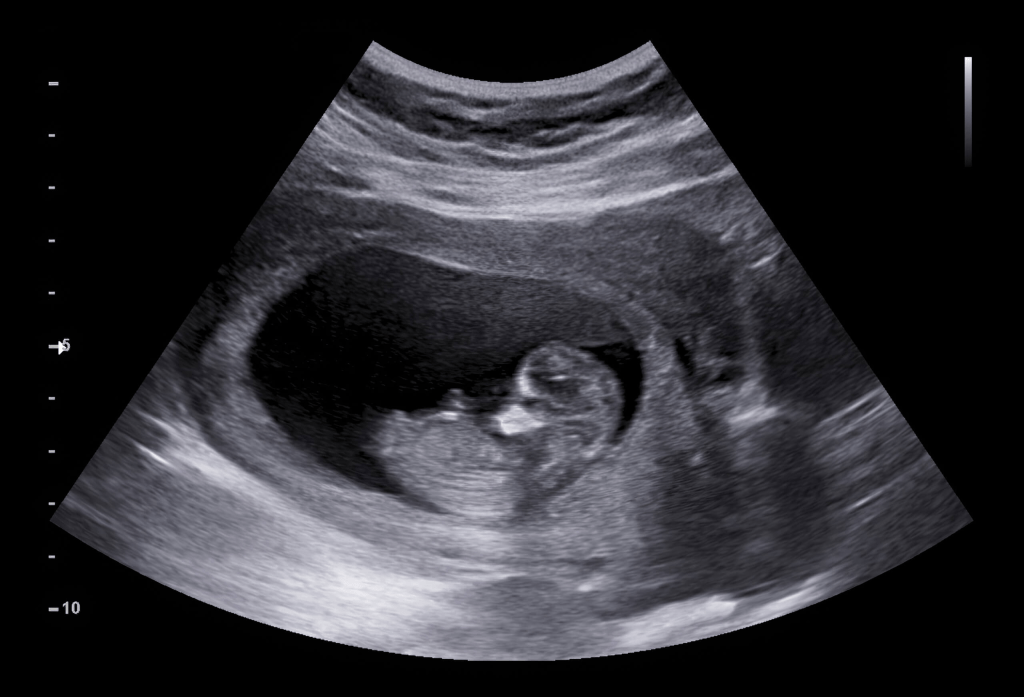

When the doctor walked in, she casually asked a few questions about how I was feeling, when my last menstrual cycle was, etc. The intent of the first ultrasound is to identify a heartbeat, collect measurements, and determine an expected due date. I had done the math prior and predicted my due date to be November 2, 2025.

As the ultrasound started, the monitor screen was facing away from me. My husband was obnoxiously hovering over the doctors shoulder, in hope to be the first to spot the heartbeat. For a solid 45 seconds, I sat there staring at everyone’s faces in the room, trying to read whether I should expect good news or bad. It was all I could do since I couldn’t see the screen. Every second felt like it lasted a decade. Finally, I said “So, is there a heartbeat!?” And the doctor turned the screen around to point at a baby whose little heart was bumping as healthy as ever. “You’re measuring to be due on November 2, 2025” she said.

Relief washed over me like a cool shower on a hot day. I stared at the screen for what seemed like forever. We took pictures and a video so we could show everyone in our family later. My husband and I smiled at each other with a kid-like excitement. The first step to a healthy pregnancy had been confirmed.